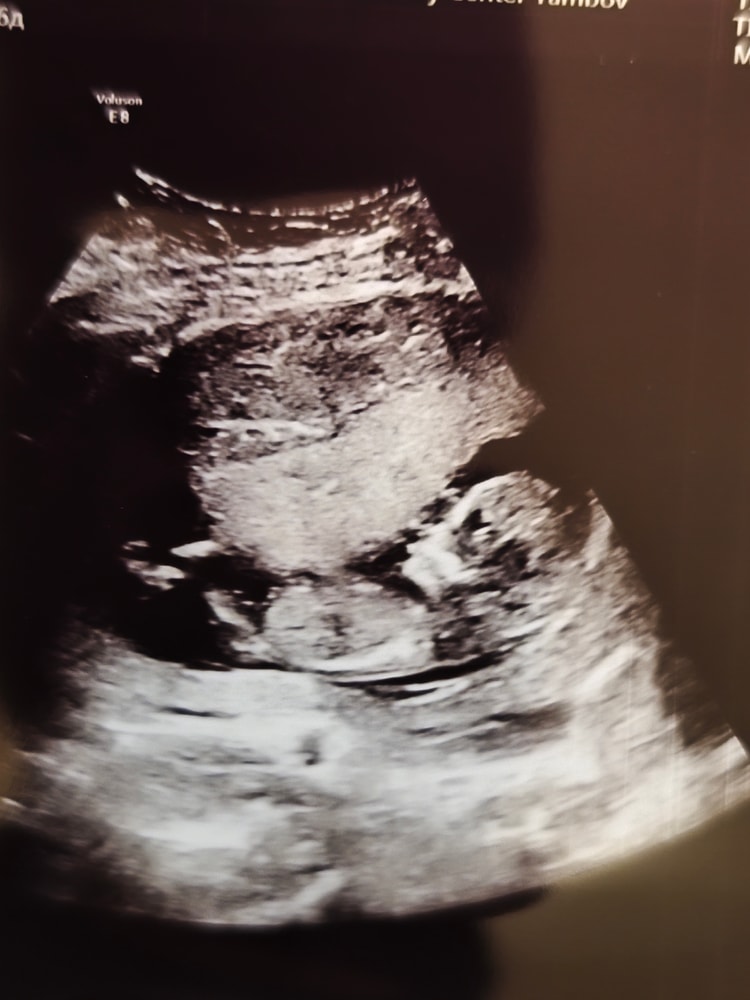

Итак ,1 скрининг пройден ♥️ Патологий по УЗИ слава Богу не обнаружено 🙏🥰

Само УЗИ длилось минут 5 , как и с дочкой, но в этот раз врач хоть что-то показывала,где голова, где ручки ,ножки. Больше сидела переживала ,чем длился сам скрининг Срок поставили 12 недель,3 дня.Теперь подробно по УЗИ:

✅КТР- 59 мм( 12 недель , 3 дня )

✅ЧСС- 172 в минуту

✅БПР- 21 мм(13 нед, 3 дня)

✅ОГ - 74 мм(13нед,1 день)

✅ТВП-1.3 мм

✅Носовая кость - визуализируется

✅ПИ в венозном протоке - 1,01

✅Хорион локализация - задняя ,правая боковая стенка

✅Место прикрепления к плаценте- центральное

✅Шейка - 36 мм

✅ПИ в маточных артериях 1,47 слева , 1, 74 справа.